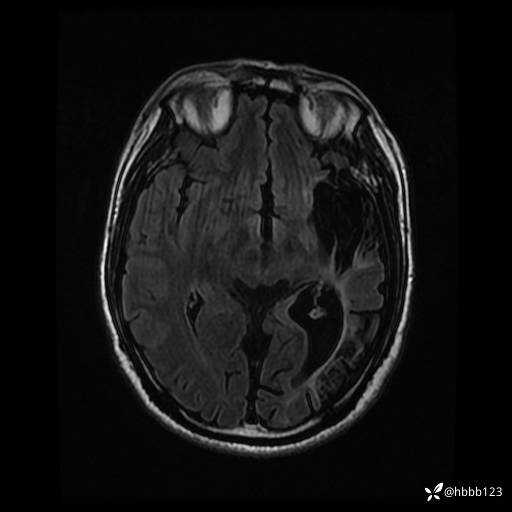

患者男,43岁。

简要病史:癫痫患者复诊,昨日发作5-6次,建议住院进一步治疗。

入院完善脑癫痫组合序列:

T2 Flair: